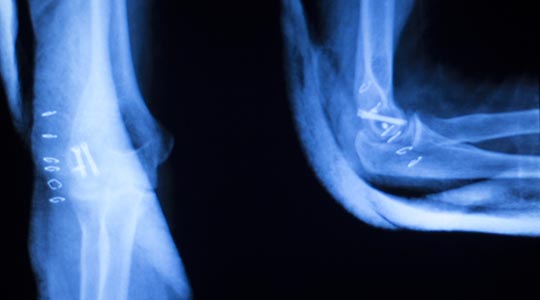

CT-scanning bliver brugt til undersøgelse af hele kroppen. Den kan fx vise komplicerede brud på knogler, forandringer i knogler eller led, blødninger og svulster, sygdomme i indre organer, betændelsestilstande og nyresten.

CT-scanning er en forkortelse for ComputerTomografi-skanning. Tomografi betyder tværsnitsundersøgelse af kroppen. Det er en avanceret røntgenundersøgelse, der giver mere detaljerede tværsnitsbilleder af kroppens forskellige væv og organer. Endvidere kan der på baggrund af de indsamlede data også laves tredimensionelle billeder.